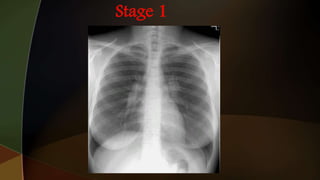

1. hilar adenopathy alone

2. hilar adenopathy plus infiltrates;

3. infiltrates alone;

4. fibrosis